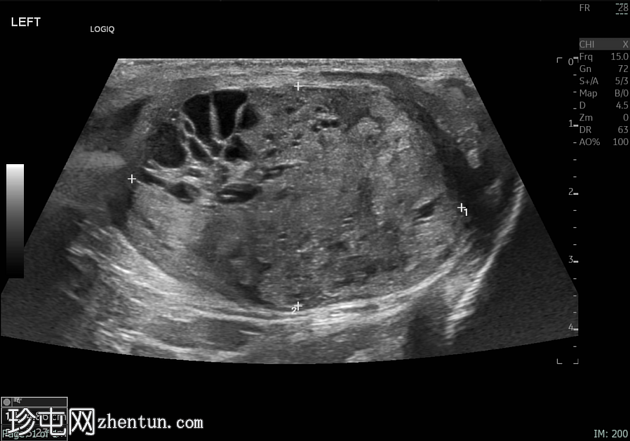

左侧睾丸肿大,体积约56 mL,可见弥漫性微结石,以及三个内部等回声病灶,伴囊性变、微钙化和明显血流信号,最大病灶大小约4.8 x 3.2 cm。

未见腹主动脉旁或髂淋巴结肿大。